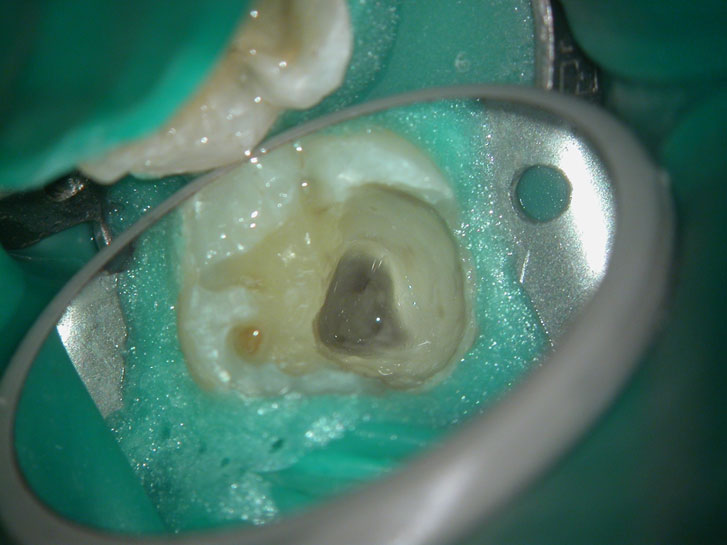

Residual caries seen after temp removal.

After caries removal

Cotton pellets placed over the palatal and Disto-buccal orifices to prevent the instrument from slipping into those canals.

Fractured instrument in mesio-buccal canal

Fractured instrument removed with ultrasonics